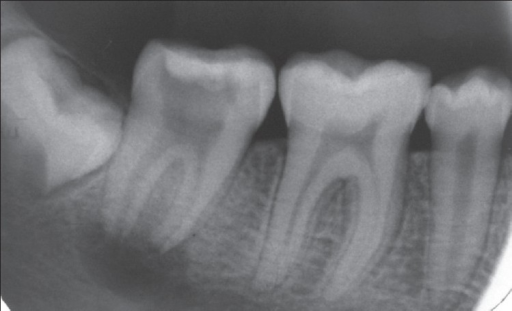

These X-rays focus on individual teeth, providing a detailed view of the entire tooth, from the crown to the root and surrounding bone.